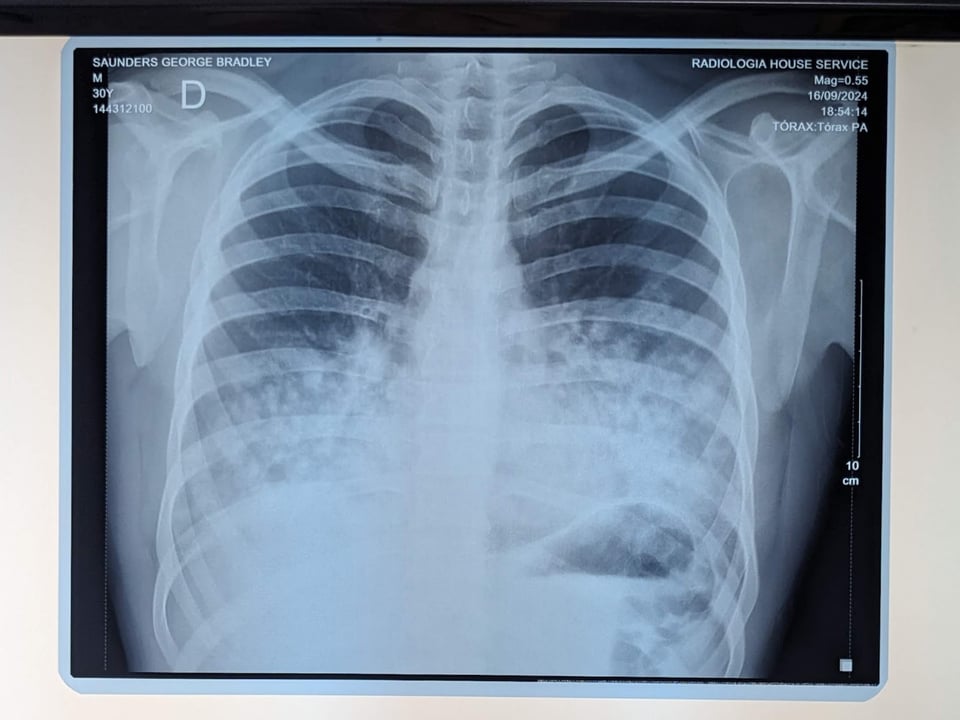

Then I was taken for blood tests and X-rays. At some point a needle was put in my stomach, I pissed in a cup, and I had these weird wires plugged into bangles and sticky cups stuck on my torso. The diagnosis was pulmonary edema - basically liquid on the lungs. The treatment was oxygen, antibiotics and rest.